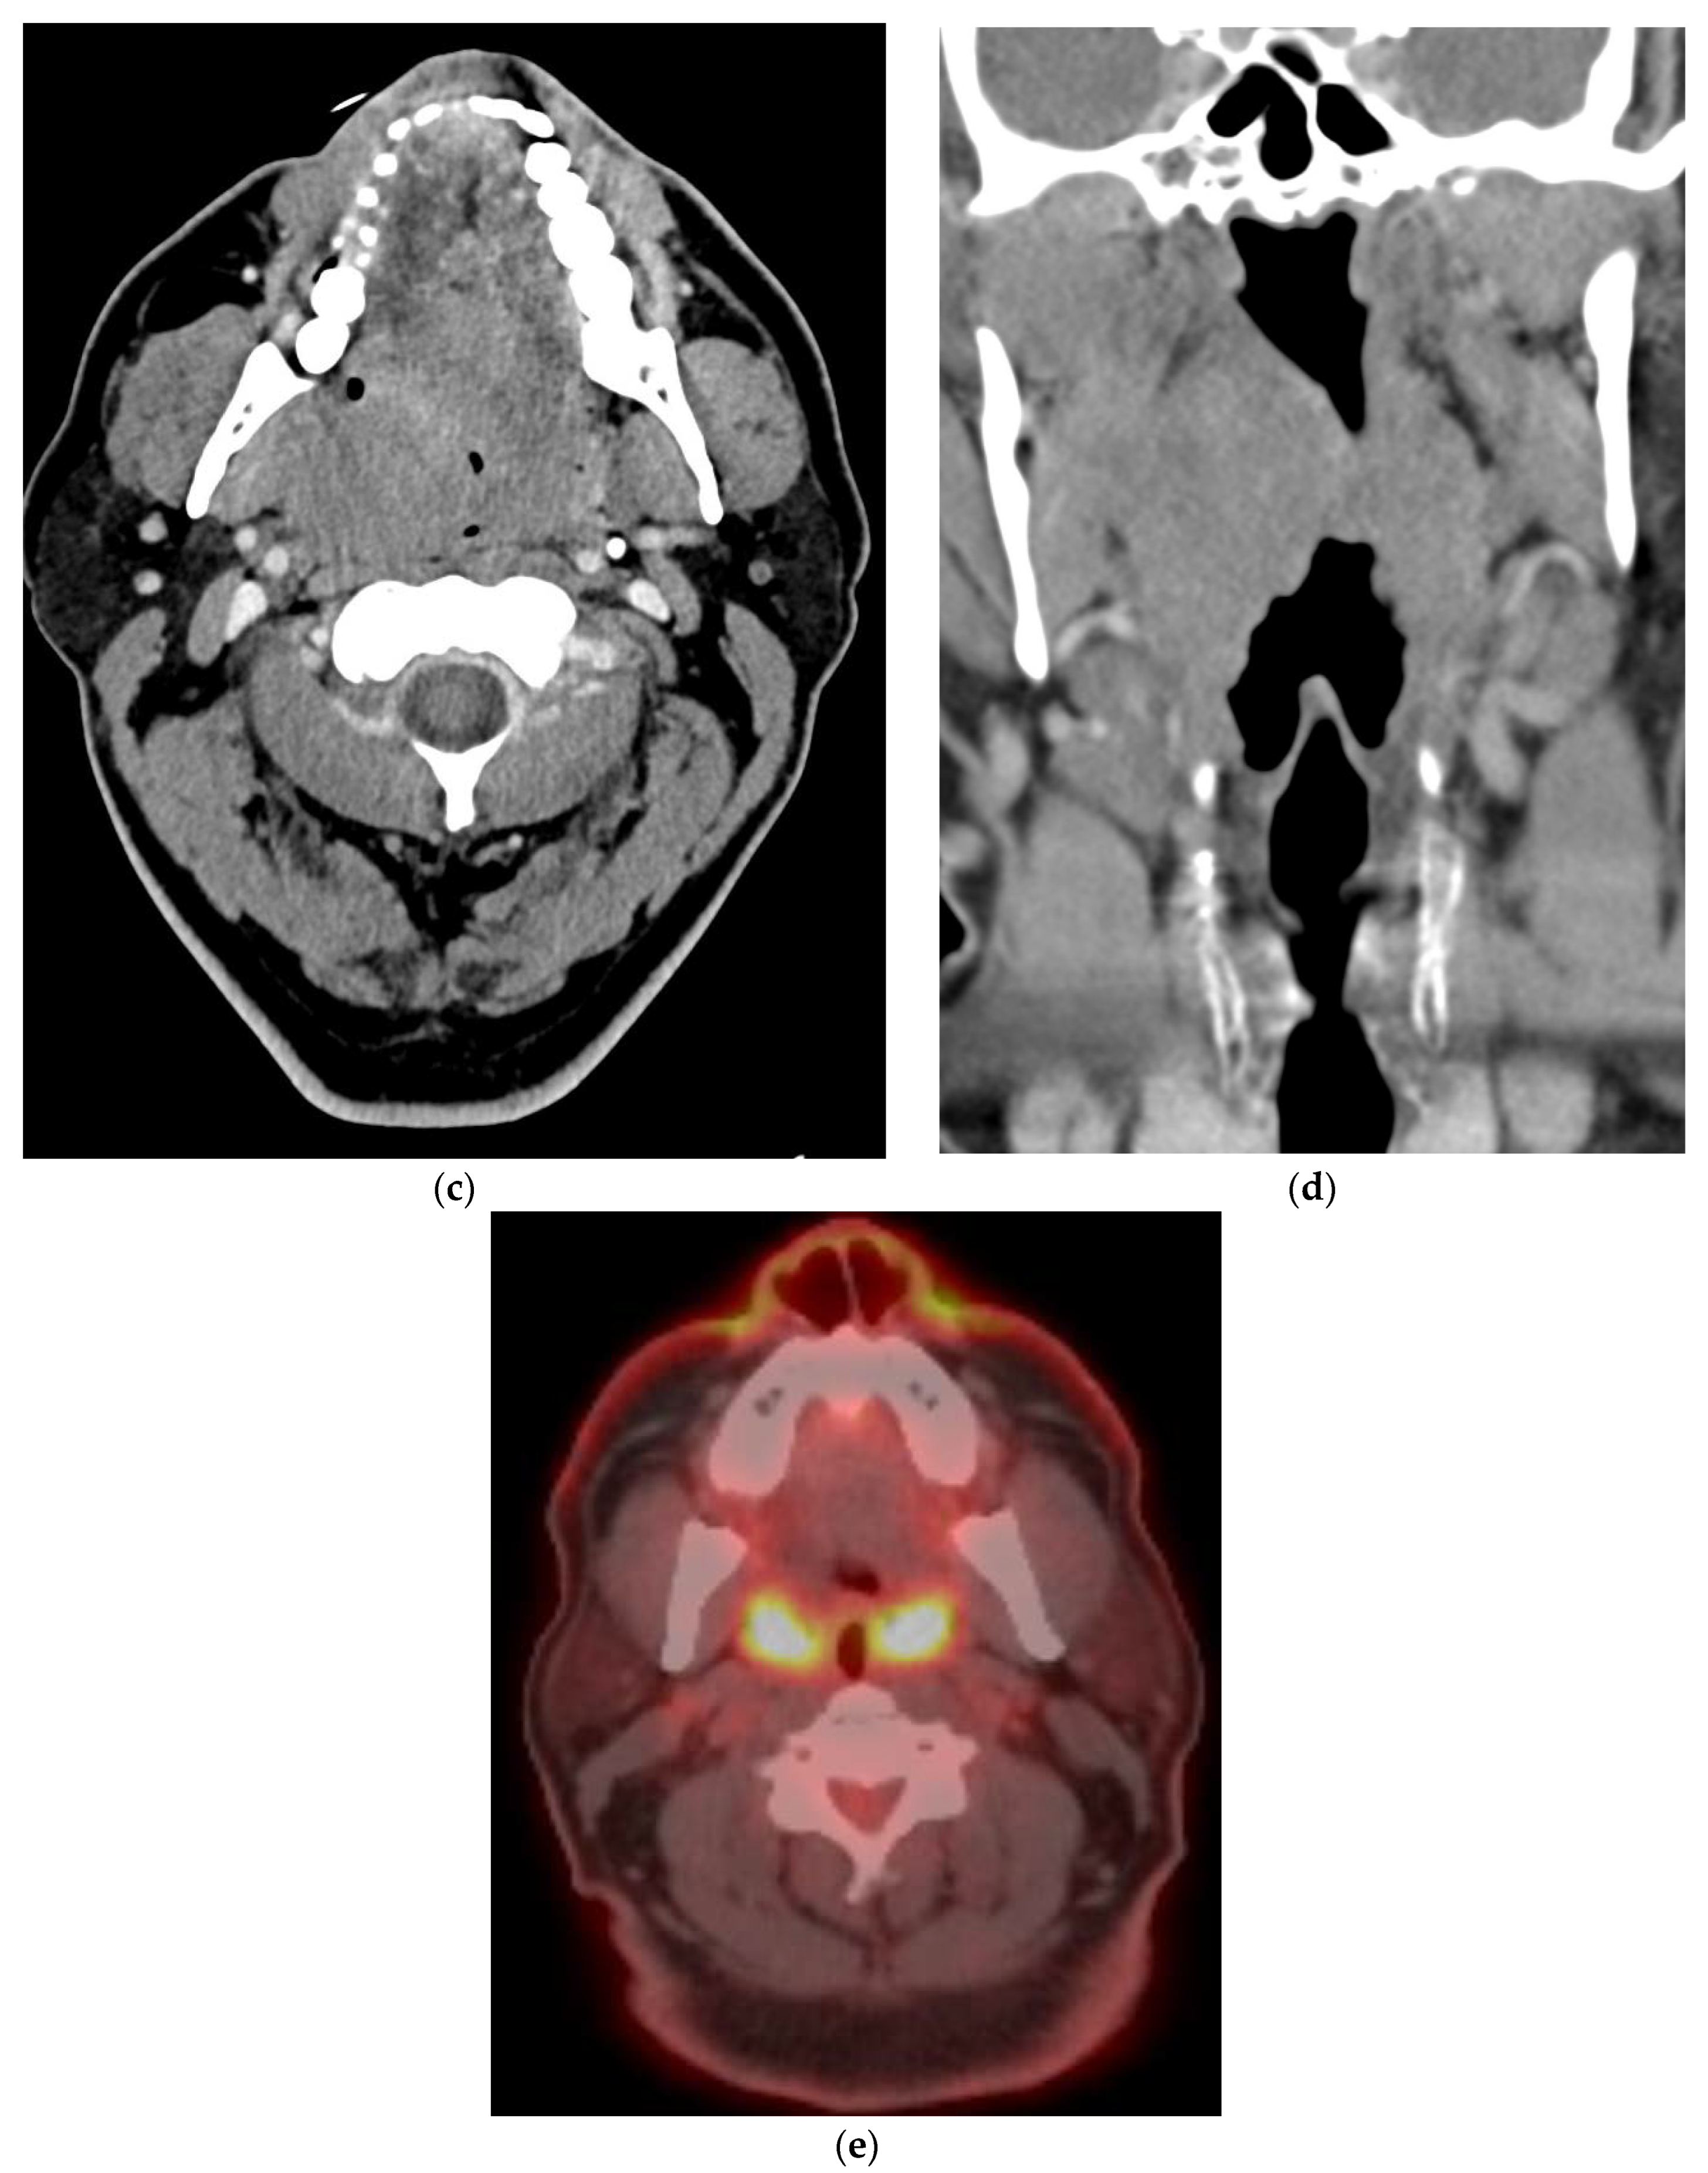

9. Disease Monitoring

- Ho, A.S.; Tsao, G.J.; Chen, F.W.; Shen, T.; Kaplan, M.J.; Colevas, A.D.; Fischbein, N.J.; Quon, A.; Le, Q.T.; Pinto, H.A.; et al. Impact of positron emission tomography/computed tomography surveillance at 12 and 24 months for detecting head and neck cancer recurrence. Cancer 2013, 119, 1349–1356. [Google Scholar] [CrossRef]

- Beswick, D.M.; Gooding, W.E.; Johnson, J.T.; Branstetter, B.F. Temporal patterns of head and neck squamous cell carcinoma recurrence with positron-emission tomography/computed tomography monitoring. Laryngoscope 2012, 122, 1512–1517. [Google Scholar] [CrossRef]